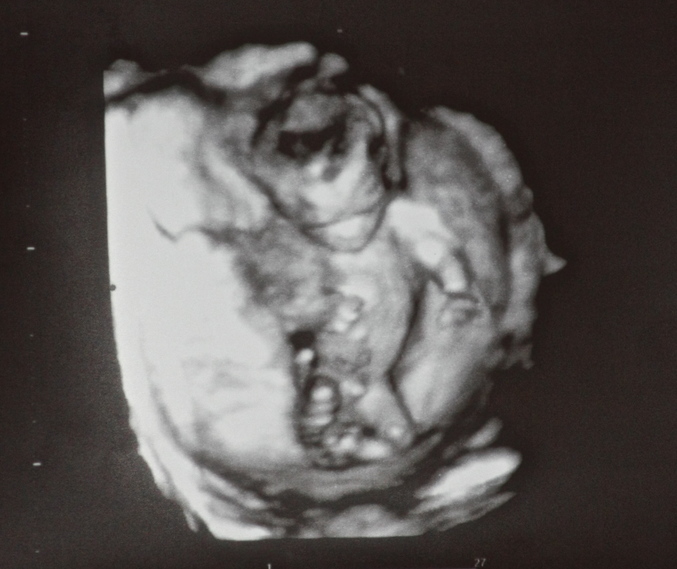

Это фото нашего малыша на 14 неделе.. Тут вроде невооруженным глазом видно.. что за узист такой..

Спасибо огромное за фотку, а то вообще не представляла, каких размеров может быть. В роддоме у новорожденных до колен видела)). У нас не 3д было, снизу смотрели.